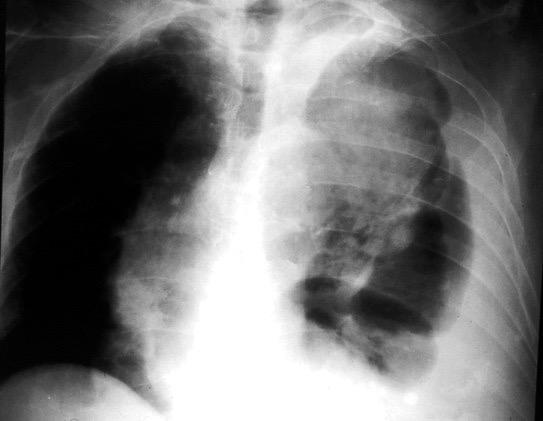

Marzo 2014: Perforación longitudinal distal secundaria a episodio de vómito (síndrome de Boerhaave). Derrame pleural izdo. que evoluciona a empiema.

Wang C-T et al. Tension hydropneumothorax in a Boerhaave syndrome patient: A case report . World J Emerg Med, 2021. Katabathina V et al. Nonvascular, nontraumatic mediastinal emergencies in adults:a comprehensive review of imaging findings. Radiographics. 2011.